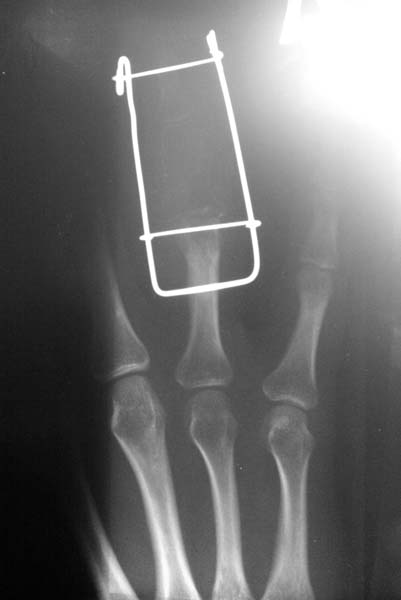

[Ortho] остеобластокластома

На данных R- граммах отсутствует практически вся средняя фаланга за исключением головки.